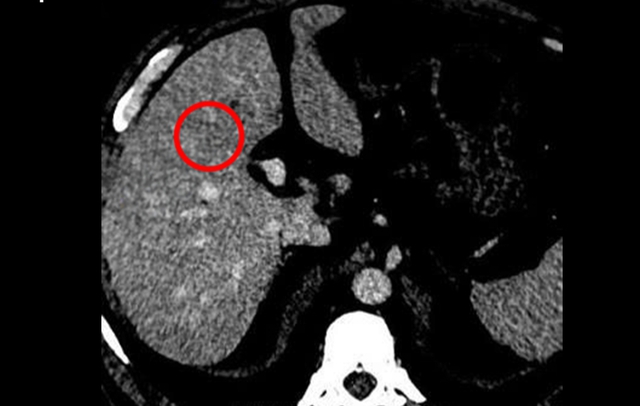

Tại đây, bác sĩ chỉ định thực hiện các xét nghiệm và chẩn đoán hình ảnh. Kết quả chụp CT ghi nhận tại gan có khối tổn thương kích thước khoảng 22 x 24 mm cùng một số nốt nhỏ khác. Để xác định bản chất, người bệnh được sinh thiết gan và kết quả giải phẫu bệnh xác định mắc ung thư gan giai đoạn sớm.

Kết quả CT cho thấy tổn thương gan (khoanh tròn). Ảnh: BVCC